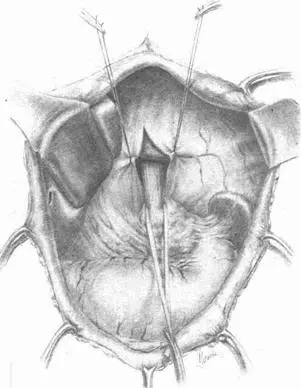

В самом деле, поворотным пунктом в развитии всей операции и главным ключом успеха является широкая мобилизация пищевода после большой сагиттальной диафрагмотомии, нередко с рассечением обеих ножек диафрагмы. Это позволяет не только выделить большой участок пищевода выше края опухоли, но допускает приблизить поле операции в момент наложения анастомоза из глубины значительно кпереди. Тот, кто хоть раз проверил это лично, никогда не откажется от этого выдающегося достижения. Попутная ваготомия часто еще более облегчает дело (рис. VIII на цветной вклейке и рис. 71–87).

Рис. 75.Сагитальная диафрагмотомия. Мобилизован пищевод

Рис. 76.Сагитальная диафрагмотомия. Анестезия и пересечение левого блуждающего нерва

Рис. 77.Сагитальная диафрагмотомия. Пересечение левого блуждающего нерва

Рис. 78.Рассечение серозного покрова тонкой кишки, указывающего место наложения швов-держалок, и наложение первого шва на тощую кишку и пищевод